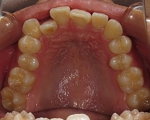

CASE5

小学1年の頃から前歯の噛み合せが逆でした。

同級生が通っていたので来ました。

(11歳/男性)↓

概要・担当医コメント:反対咬合・前歯部咀嚼障害↑

/マルチブラケット装置/非抜歯/動的治療期間24ヶ月(25回)/費用概算:60万円

治療前は虫歯のコントロールが難しい状態でしたが,矯正治療を開始してからは歯磨きを丁寧にしてくれるようになり,甘味摂取習慣の改善も行って頂いた効果があり,その後の虫歯の発生は無く現在に至っています.